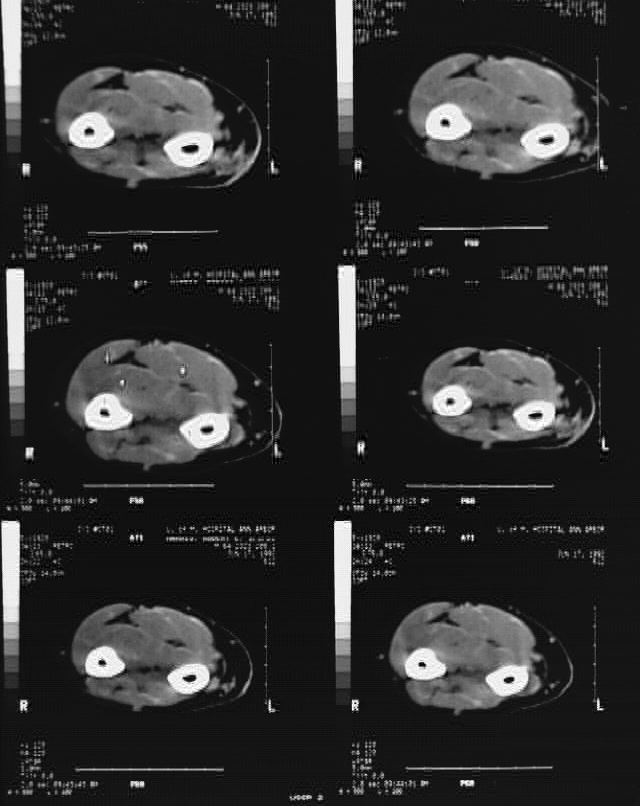

Radiology Images

Upper Limbs: Arm CT Film 8: